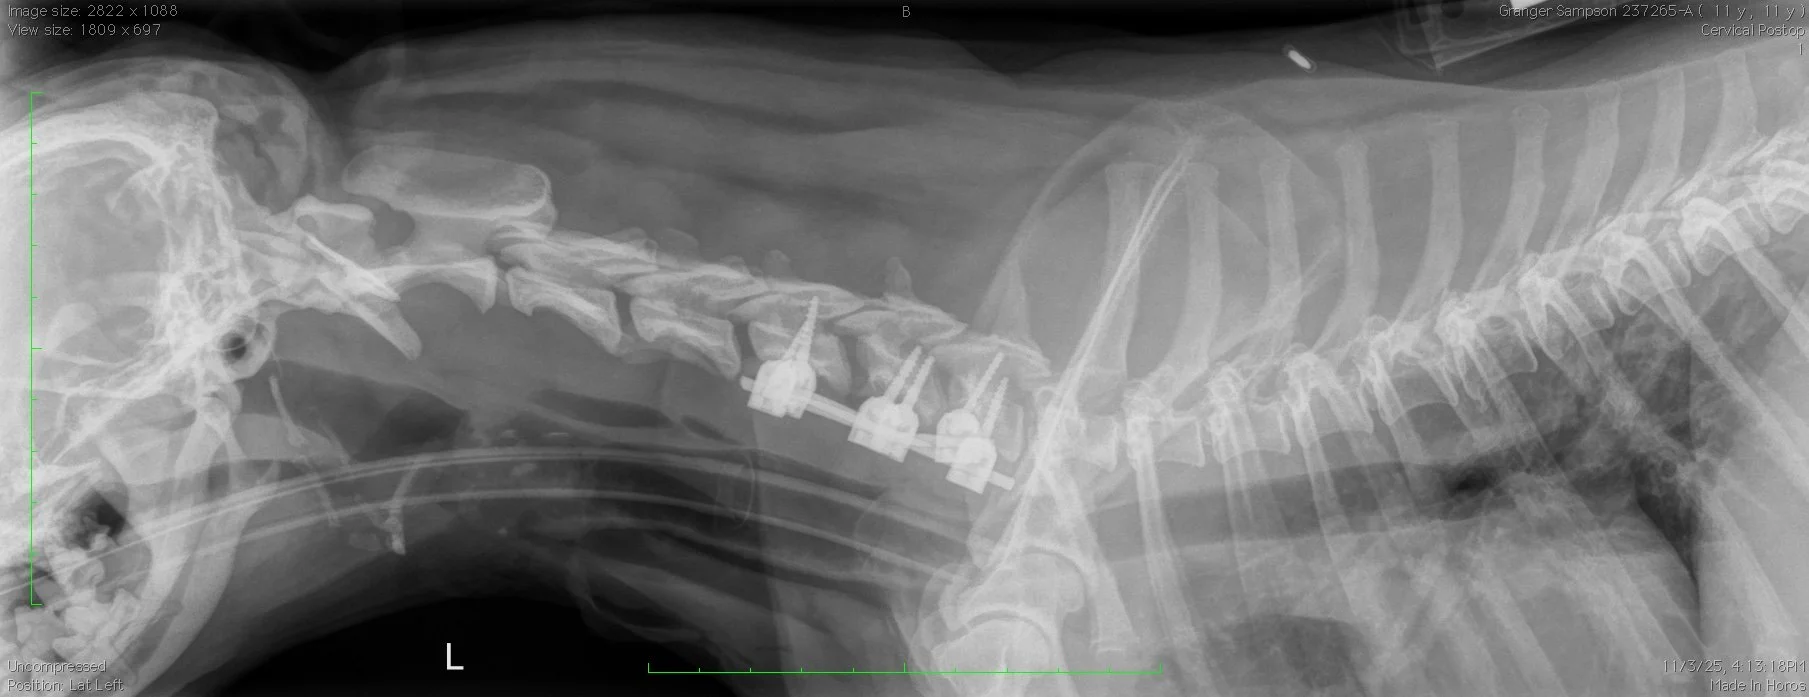

5 kg Pug subtotal corpectomy with stabilization

7 kg French Bulldog dorsal laminectomy with stabilization

8 kg Shih Tzu, C5 - C7 stabilization

8 kg French Bulldog, dorsal laminectomy and stabilization